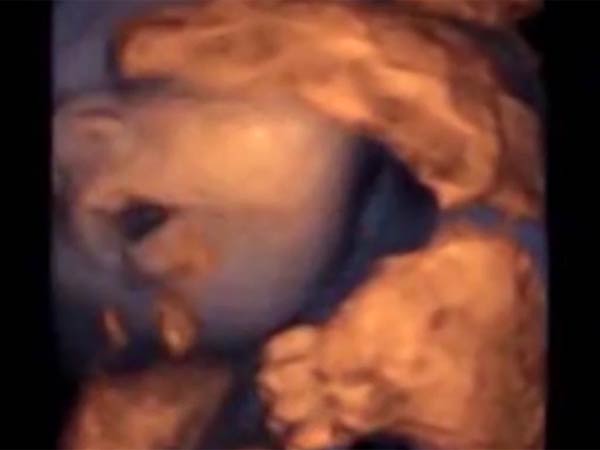

ஆனால், இவ்வாறு இசையைக் கேட்கும் வயிற்றில் இருக்கும் குழந்தைகள் அதற்குப் பாட்டுப் பாடுவது போல் வாயசைப்பது வீடியோ ஒன்றில் பதிவு செய்யப்பட்டுள்ளது.

ஸ்பெயின் நாட்டிலுள்ள பார்சிலோனா ஆராய்ச்சியாளர்கள் இந்த ஆய்வை நடத்தியுள்ளனர். இது தொடர்பாக அவர்கள் வெளியிட்டுள்ள வீடியோ ஒன்றில், இசையைக் கேட்டு வயிற்றில் உள்ள குழந்தை ஒன்று வாயை அசைத்து பாட முயற்சிப்பது போல் உள்ளது.

இந்த ஆய்வை தலைமையேற்று நடத்திய டாக்டர் மாரிசா லாப்சி இது தொடர்பாக கூறுகையில், ‘கர்ப்பத்தில் இருக்கும் 16 வார சிசு இசையைக் கேட்டு வாயை மற்றும் நாக்கை அசைப்பது கண்டுபிடிக்கப்பட்டுள்ளது. இது பார்ப்பதற்கு அக்குழந்தைப் பாட அல்லது பேச முயற்சிப்பது போல் தெரிகிறது.